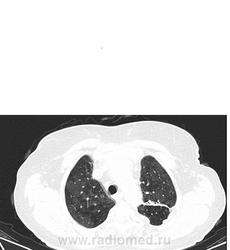

Мне видится хроническая ТЭЛА-упорно зрю мозаичность, видится сумасшедшая легочная гипертензия, застойные сердечные дела, и о ужас... мерещится мезотелиома... все эти узелки по плевре, каплевидны формы, прям по междолевочке... да и шарик в печени - али не гиповаскулярный метастаз???

ну неужели мои глюки и гипердиагностика??? не може же быть такое количество осумкованных плевритов???

ТЭЛА без контраста не исключишь. При таком гидротораксе добавил бы исследование на животе (или на боку, если ей это легче). Кстати, а почему сразу мезотелиома? А в легких застой и отек.

мезотелиома злокачественная сопровождается рецидивирующим большим гидротораксом, а доброкачественный вариант выглядит не так . Тут мне видится междолевой и костальный плеврофиброз , осумкавание жидкости по заднебоковой поверхности , возможно. На счет легких согласна с предыдущим мнением, хотя на счет отека у меня не повернулся бы язык.

В легких - мозаичный паттерн.

ЧТо это такое - это чередование повышенной(по типу матового стекла) и пониженой плотности в легочной ткани - неравномерные, неправильной формы (пятнистого - "patchy" характера).

Первое (и самое главное), что мы должны сделать когда видим такие изменения на КТ, это определиться - какие зоны при этом паттерне являются патологическими:

- патологическими являются зоны повышенной плотности (то есть мы видим участки уплотнения легочной ткани по типу "матового стекла" за счет частичного заполнения воздухоносных путей - жидкостью, клетками, фиброзом ) Зона пониженной пониженной плотности - это "нормальная" легочная паренхима.

- патологическими являются зоны пониженной плотности и обусловлены они нарушением перфузии указанных участков первичного или вторичного характера: первичного - при ТЭЛА (чаще всего ХТЛГ) - когда имеется обструкция сосудов и возникает первичная олтгемия, вторичного при обструктивных изменениях мелких бронхов и бронхиол - при этом просходит реактивное уменьшение и диаметра легочных сосудов (реактивня олигемия).

Во втором сучае (то есть если патологическими являются участки пониженной плотности)- мы имеем право обзывать этот паттерн - "мозаичной перфузией" - так как он обусловлен именно нарушеним перфузией.

- характер мозаичного паттерн. Для ХТЛГ больше характерна мозаичная перфузия с наличием сегментарных и субсегменатрных участков повышенной и пониженной плотности (как в этом случае)

В вышеприведенном случае - явных КТ-данных за наличие отек - я не вижу.

Вообщим на мой взгляд - ХТЛГ возможно рецидив.